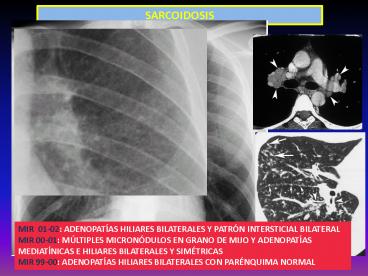

SARCOIDOSIS

MIR 01-02 ADENOPATÍAS HILIARES BILATERALES Y

PATRÓN INTERSTICIAL BILATERAL MIR 00-01

MÚLTIPLES MICRONÓDULOS EN GRANO DE MIJO Y

ADENOPATÍAS MEDIATÍNICAS E HILIARES BILATERALES Y

SIMÉTRICAS MIR 99-00 ADENOPATÍAS HILIARES

BILATERALES CON PARÉNQUIMA NORMAL